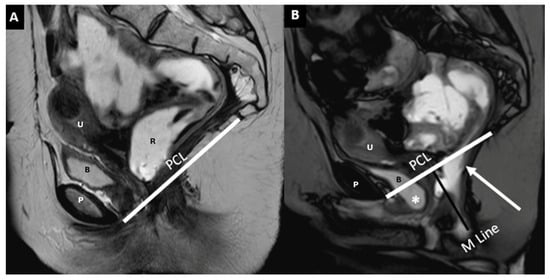

| Component/Reference Line | Definition | Role in HMO System | Normal Range/Severity/Staging |

|---|---|---|---|

| Pubococcygeal Line (PCL) | Line from the inferior pubic border to the last coccygeal joint | Baseline for measuring organ descent | PCL Compartment Staging Stage 0: Above PCL Stage I: Descent <3 cm below PCL Stage II: Descent 3–6 cm below PCL Stage III: Descent >6 cm below PCL Stage IV: Complete organ prolapse |

| Mid-pubic Line (MPL) | Line drawn through and caudad through the axis of the mid-pubic symphysis on sagittal MRI | Used to assess pelvic organ prolapse (POP); a 90° angle is measured between MPL and the bladder, vaginal vault, and anterior anorectal junction | MPL Compartment Staging Stage 0: >3 cm above MPL or TVL −2 cm Stage I: 1 cm above ≤ X ≤ 1 cm below MPL Stage II: 1 cm above ≤ X ≤ 1 cm below MPL Stage III: ≥1 cm below MPL Stage IV: Complete organ prolapse |

| H Line (Hiatal Line) | Distance between the inferior pubic border and the anorectal junction | Assesses puborectal hiatus (anteroposterior dimension during straining) | POP Grade Hiatal Enlargement Normal: <6 cm Mild: 6–8 cm Moderate: 8–10 cm Severe: >10 cm |

| M Line (Muscle Line) | Perpendicular line from the PCL, measuring organ descent | Evaluates posterior pelvic organ descent | Pelvic Floor Descent Normal: <2 cm Mild: 2–4 cm Moderate: 4–6 cm Severe: >6 cm |